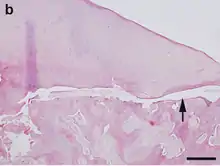

Pathological specimen from a sow— the arrow points to a fracture in the lateral epicondyle of the humerus.

Hematoxylin and eosin staining. Bar = 200 μm.